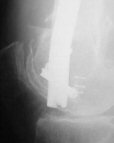

A new toy is more interesting and fashionable. And anyway it is not panacea, i have already seen presentations with LISS failures like the attached one presented by D.Seligson. And people also demonstrated incisions say that the method is not so LESS invasive as it supposed to be.